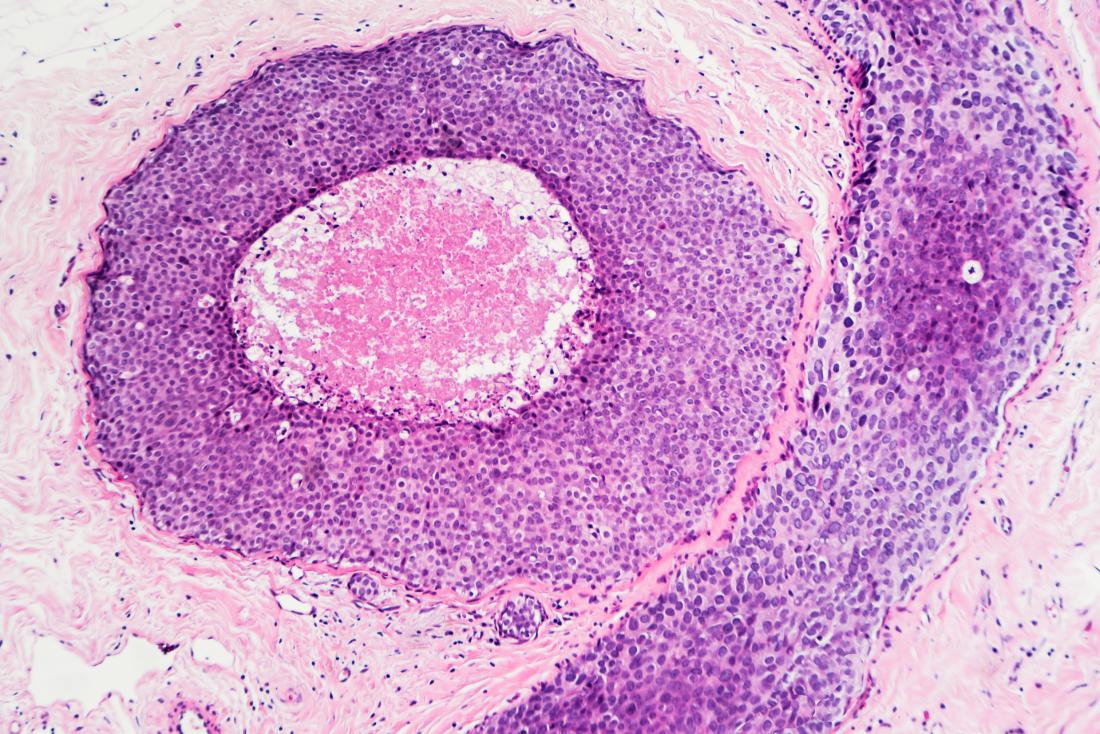

Alcune forme di cancro causano escrescenze visibili chiamate tumori, mentre altre, come la leucemia, non lo fanno.